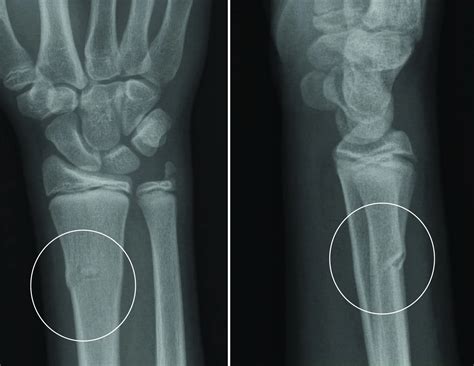

A buckle fracture wrist is a type of incomplete fracture that occurs when the bone bends and breaks on one side, causing the other side to bulge outward. This type of fracture is also known as a torus fracture or a stable fracture. It is most commonly seen in children because their bones are more flexible and less dense than those of adults. However, adults can also experience buckle fractures, especially in situations involving high-impact forces.

Buckle fractures typically occur in the distal radius, which is the larger of the two bones in the forearm and is located near the wrist. The injury usually results from a fall onto an outstretched hand, where the force of the impact causes the bone to bend and break. Despite being an incomplete fracture, a buckle fracture can still cause significant pain and discomfort, requiring proper medical attention and treatment.

• Imaging Tests: X-rays are the primary imaging tool used to diagnose buckle fractures. They can provide clear images of the bone, allowing the healthcare provider to identify the location and extent of the fracture. In some cases, additional imaging tests such as CT scans or MRIs may be ordered to get a more detailed view of the injury.